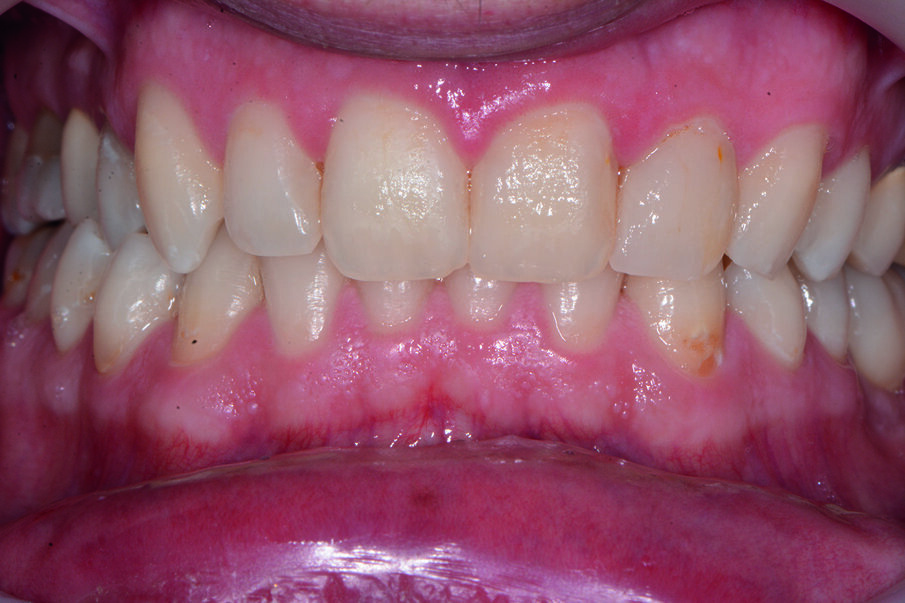

Durante l’esame obiettivo (Figg. 1a, 1b) rileviamo il danno iatrogeno da terapia ortodontica precedente alla visita e riscontriamo la presenza di processo carioso ICDAS 3 in zona 33 e in zona 47, white spots in zona 31 e 41. Durante l’esame obiettivo, l’ausilio della videocamera intraorale Sopro-Care (Acteon) permette, tramite filtri appositi, di evidenziare in modo rapido e accurato le zone di demineralizzazione e le aree infiammate e di mostrarle al paziente in real time, rendendolo attivamente partecipe e consapevole della situazione clinica (Figg. 2a-2f). I ricercatori del Baylor College of Dentistry hanno dimostrato che il 23,4% dei pazienti ha sviluppato almeno una white spot lesion durante il trattamento ortodontico.

Chiediamo al paziente se si fosse sottoposto a terapia ortodontica e il paziente riferisce di essersi sottoposto a terapia ortodontica in età adolescenziale per circa 2 anni e di non aver dato molta importanza alle lesioni presenti, poiché non aveva avuto grande sintomatologia riteneva che le white spots presenti non fossero un segno di demineralizzazione. Alla domanda della causa delle lesioni riferiamo che un inefficace controllo di placca domiciliare e uno stile di vita alimentare cariogeno, alzava il rischio di demineralizzazione delle lesioni che probabilmente erano state provocate dall’apposizione delle bande ortodontiche con materiale non di ultima generazione come i cementi vetroionomerici in grado di liberare fluoro. Inoltre riferiamo che durante la fase terminale del debonding, la topografia delle lesioni faceva presupporre l’uso poco attento di frese che avevano danneggiato lo smalto. Il paziente si mostra motivato e chiede una soluzione terapeutica che abbia come obiettivo la risoluzione funzionale ed estetica più veloce possibile. Viene condiviso con il paziente il piano terapeutico e proponiamo di iniziare con la terapia parodontale non chirurgica. Concordiamo con il paziente tempi, modalità di utilizzo e strumenti per migliorare il management degli stili di vita domiciliari, per il controllo chimico e meccanico del biofilm batterico (Nardi GM, Sabatini S, Guerra F, Tatullo M, Ottolenghi L. Tailored Brushing Method (TBM): an innovative simple protocol to improve the oral care. J Bio- med 2016; 1:26-31).